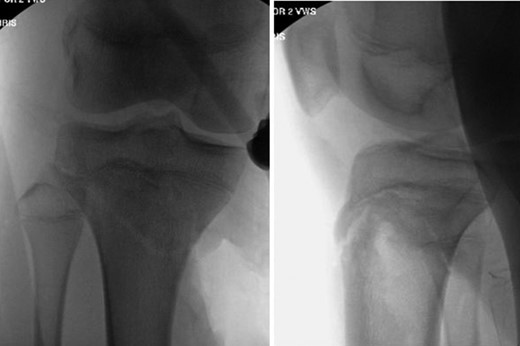

Patient is a 14-year-old male who slipped and fell while jumping off of a diving board and landed onto a flexed right knee. The patient was stable on presentation and neurovascularly intact with the knee locked in flexion. Skin was tenting anteriorly over the tibial tubercle and his compartments were swollen but compressible. A single plain film view (Fig. 1) was obtained prior to orthopaedic consultation. Closed reduction under sedation and splitting was attempted in the ED with partial but unsatisfactory improvement. Post-reduction radiographs (Fig. 2) demonstrated a tibial tubercle fracture with extension through the entire proximal tibial physis with metaphyseal involvement posteromedially. We classified this as a type IV tibial tubercle fracture, Salter–Harris II variant. In conjunction with patient and family we planned for urgent closed versus open reduction and application of knee-spanning external fixator. Immediately prior to surgery in the pre-operative holding area, the patient noted increasing right leg pain. In the operating room (OR), a marked increase in swelling with tense skin was observed. Due to rapidly progressive swelling and nature of the fracture, the decision was made to proceed with a 4-compartment fasciotomy of the right leg. The medial-sided fasciotomy (Fig. 3) revealed significant bulging of the superficial and deep compartments; however, the anterior and lateral compartments were less swollen. The fracture was unable to be closed reduced intraoperatively, therefore proximal extension of the medial fasciotomy wound was performed to open and reduce the fracture under direct visualization. Anatomic reduction was achieved and a knee-spanning external fixator was applied (Fig. 4). Approximately 72 hours later the patient was brought back to the OR for irrigation and debridement, lateral wound closure, and medial wound vacuum placement. Another 72 hours later, he returned to the OR for removal of the external fixator, ORIF, and split-thickness skin grafting of the medial fasciotomy site. An anterolateral approach was used with a 3.5 mm proximal tibial locking plate (Fig. 5). At most recent follow-up (Fig. 6), six months post-op, the patient is pain free, ambulating without assistive device, and has returned to all desired activities.

AP and lateral radiographs following open reduction and application of knee-spanning external fixator.